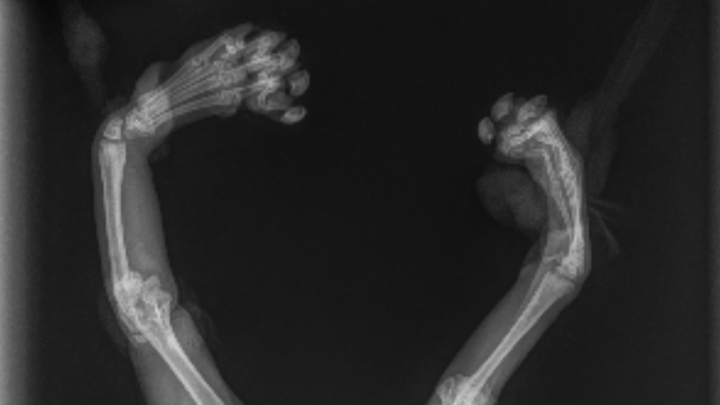

Pebbles is a tiny, determined kitten with radial hypoplasia, a rare condition that causes her front legs to bend inward. Despite her challenges, she lives life with joy, curiosity, and an unbreakable spirit—earning her the nickname “Pebbles the Meerkat.”